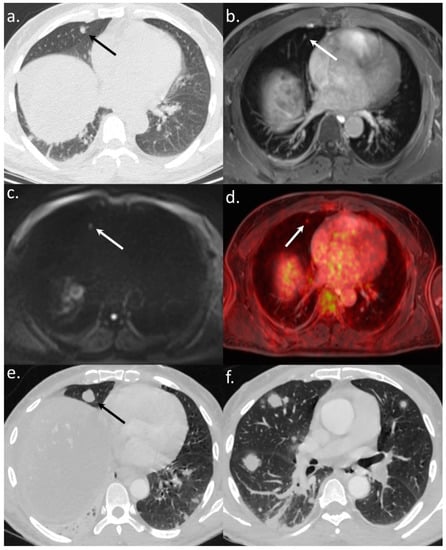

Figure 2. A 56-year-old patient referred to WB-PET/MRI before TARE. The CT-CAP (a) showed a solitary rounded 7 mm-size lung nodule (arrows). The WB-PET/MRI confirmed an infracentimetric lung nodule visible on morphologic sequences (T1-weighted after gadolinium injection) (b) with hyperintensity on b800 s/mm2 DWI (c) and 18F-FDG hypermetabolism (d) leading to the diagnosis of lung metastasis. The followup CT scan (e,f) performed three months after the WB-PET/MRI showed a significant progression of the number and size of lung nodules, confirming the metastatic status.

All 14 metastatic sites were correctly identified on the WB-PET/MRI, although only 7 of 16 individual pulmonary metastases (44%) were seen (Figure 2). On the CT-CAP/liver MRI dataset, six metastatic sites were correctly identified (6/14; 43%), resulting in a significantly lower sensitivity (43% vs. 100%, p = 0.002). Notably, all 10 individual bone metastases were missed on the CT-CAP/liver MRI (Figure 3), as well as two mediastinal lymph nodes (Figure 4) and one retroperitoneal lymph node involvement (Figure 3).

The WB-PET/MRI lead to changes in therapeutic management in 10 of 104 patients (9.6%). Metastatic lesions were identified by the WB-PET/MRI in two BCLC stage C patients referred before liver transplantation (Figure 3) and in five BCLC stage C patients referred before TARE (Figure 2 and Figure 4).